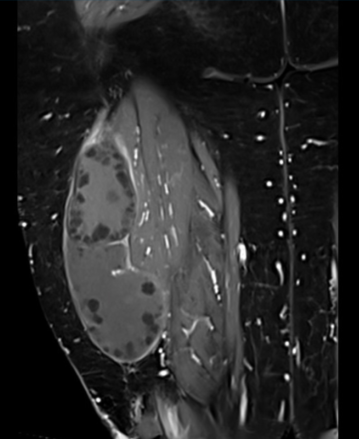

Se presenta el caso de una paciente de sexo femenino de 70 años, procedente de zona rural con diagnóstico clínico imagenológico de quiste hidático primario músculo-esquelético en muslo. La resonancia magnética (RM) (figura 1) y (figura 2) evidenciaba la presencia de una lesión isointensa en T1, de aspecto quístico, en el espesor del músculo bíceps femoral, inmediatamente por detrás del tabique intermuscular lateral. En la (figura 1) se evidencia corte axial de RM en secuencia T1 con saturación de la grasa. Se puede apreciar la relación en profundidad con ramas de las arterias perforantes, colaterales de la arteria femoral profunda. En la (figura 2) se evidencia corte coronal de RM en secuencia T1 con saturación de la grasa con gadolinio que evidencia realce de la pared y algunos septos incompletos. La tomografía computada no evidenciaba enfermedad a nivel hepático y/o pulmonar. La paciente había recibido tratamiento previo con albendazol.

La imagenología constituye un pilar diagnóstico fundamental, destacándose el uso de la ecografía, tomografía computada (TC) y RM (68% vs. 32% vs. 72%). De la revisión, en más de la mitad de los pacientes (n=15, 60%) se solicitaron dos estudios de imagen complementarios. La RM fue el estudio más solicitado, formando parte del algoritmo diagnóstico de las tumoraciones de partes blandas. Permite determinar el tamaño del quiste, y fundamentalmente sus relaciones musculares, vasculares y nerviosas, siendo una herramienta clave a la hora de planificar abordaje y táctica quirúrgica8,9. El quiste hidático se visualiza como una lesión quística cuya pared es hipointensa en comparación con el líquido intraquístico en secuencia T1. Es frecuente el hallazgo de vesículas prolígeras en su interior, como se observa en las (figura 1) y (figura2), que en T1 son hipointensas respecto a la matriz del quiste9. Se ha descrito en esta topografía la presencia del signo del camalote (water-lily sign), clásicamente comentado para quistes hepáticos o pulmonares. Puede verse edema perilesional por compresión o reacción inflamatoria de los tejidos adyacentes10. En todos los pacientes se asoció una ecografía de abdomen y/o tomografía de tórax y abdomen a fin de descartar enfermedad hepática o pulmonar sincrónica.